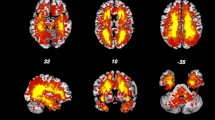

Figure 1A and Table 3 demonstrate PN1 identified in HCs consisted of 10 regions that are a subset of the previously defined hubs Table 2. Figure 1A shows that the connectivity of PN1 predominantly includes inter-hemispheric connections with important intra-hemispheric connections. We used the same loading threshold (0.1) to identify PN1 in each MS group. In RRMS and PPMS, PN1 is the same as in HCs, whereas in SPMS a loss of the right thalamus was detected (Fig. 1A, Table 3 and eFig. e1 Supplemental Results).

The first and second principal network in healthy controls and multiple sclerosis subtypes. (A) There is a loss of the right thalamus in the first principal network in SPMS. (B) For the second principal network, there is a loss of the right putamen connections in all MS subtypes, and an additional loss of the right thalamus in SPMS. Intensity of the edges’ colour denotes the strength of the connection. Abbreviations: HCs = healthy controls; RRMS = relapsing-remitting MS; PPMS = primary progressive MS; SPMS = secondary progressive MS. Reproduced from Charalambous44.

Figure 1B and Table 4 show that PN2 in HCs is comprised of 10 brain regions that are very similar to PN1 with the exception of the right putamen and left thalamus. Specifically, the right putamen is identified as network hub in PN2 while the left thalamus no longer qualifies. Additionally, PN2 is comprised of regions with strong intra-hemispheric connections (Fig. 1B). In all MS subtypes, this network did not include the right putamen compared to HCs, while in SPMS group there was additional loss of the right thalamus (Fig. 1B and eFig. 2 Supplemental Results).